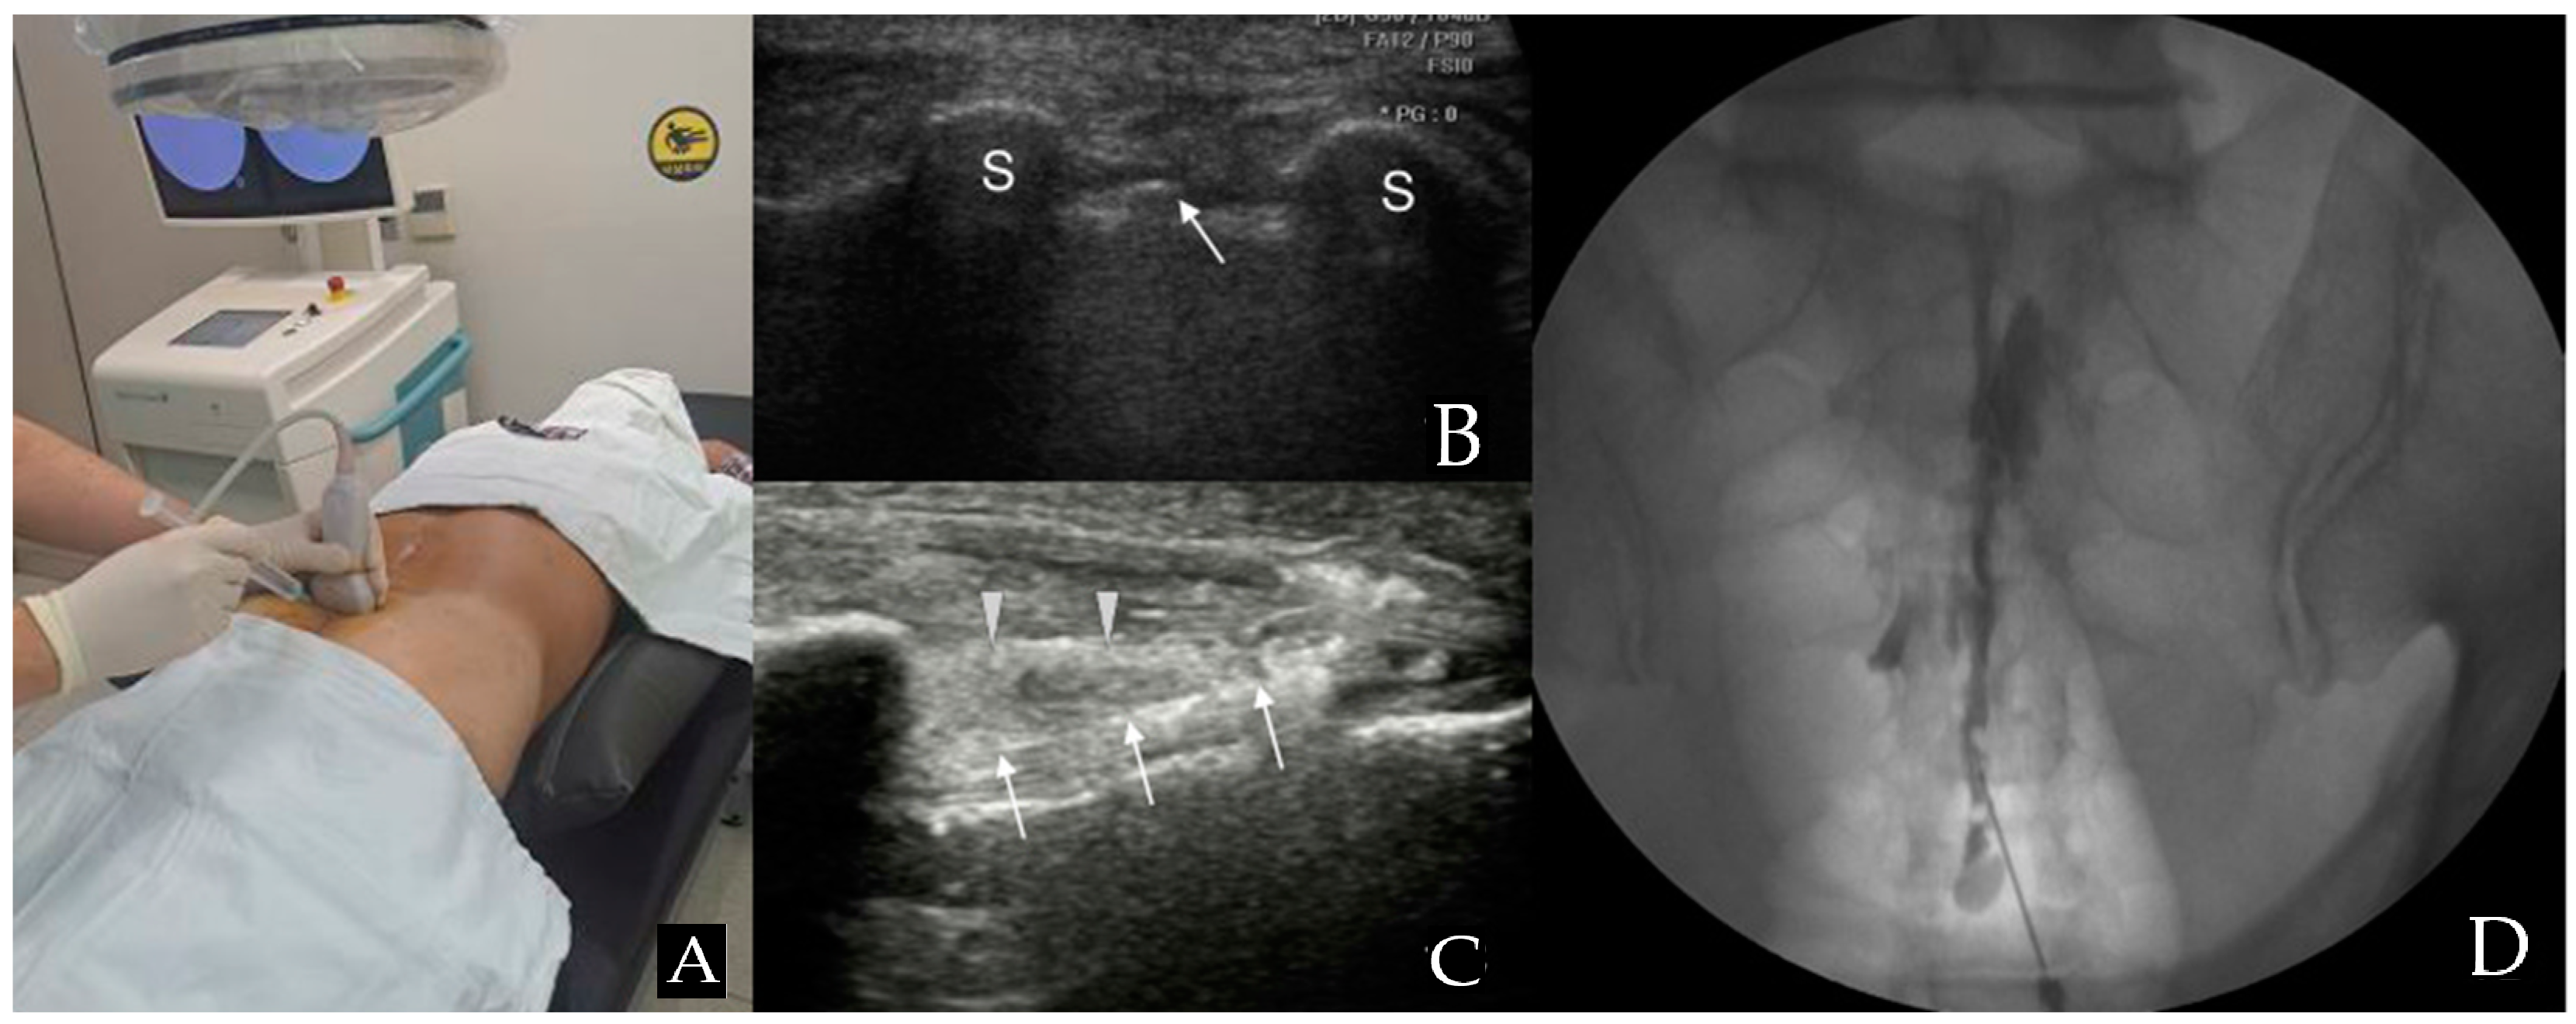

Patients were positioned prone, and the RS80A (Samsung Medison Co., Ltd., Seoul, Republic of Korea) with a linear array transducer (3–12 MHz) was used for US imaging. Before injection, US was used to verify anatomical variations, ensuring proper needle length and diameter selection for the caudal portal. The US transducer was initially positioned at the midline to acquire a transverse view of the sacral hiatus [9,10] (Figure 1A). The sacral hiatus was identified in the US images based on specific landmarks. In the transverse section, the two sacral cornua appeared as two hyperechoic structures, forming an inverted U shape [2,9,10,11]. Additionally, color Doppler imaging was used to identify blood vessels.

Figure 1.

Combined ultrasound and fluoroscopy-guided caudal epidural steroid injection. (A) Utilizing ultrasound transverse view to insert the spinal needle in the appropriate location. (B) Ultrasound image seen from the probe in (A) position. The arrow points to the caudal epidural needle, which is located between the two sacral cornua, indicated by S (hyperechoic reversed U shape) in the image. (C) A view along the longitudinal axis displays the needle within the caudal epidural space. The arrowhead is pointing to the sacrococcygeal ligament, while the arrow points to the caudal epidural needle. (D) An anteroposterior X-ray reveals the contrast medium’s epidural spread following the administration of a caudal epidural injection.

With the assistance of another medical staff member, the interventionalist, wearing sterile gloves, arranged the equipment on a sterile covering. The sacrococcygeal area was sterilized with iodine-based povidone and alcohol solutions. The location of the sacral cornu was confirmed through palpation. Finally, the needle was inserted toward the affected side to deliver the medication toward the specific side and optimize the medication’s chances of reaching the anomaly site [2]. A 22-gauge, 90 mm spinal needle (SP.QB, Taechang Industrial Co., Ltd., Chungnam, Republic of Korea) was then inserted between the two cornua into the sacral hiatus (Figure 1B). Once the sacrococcygeal ligament was successfully penetrated, often accompanied by a pop or give sensation, the transducer was rotated to attain a longitudinal view of the sacrum and sacral hiatus. The needle was then advanced into the sacral canal under real-time US guidance (Figure 1C) [2,9,10,11].

After needle insertion, it was crucial to verify the absence of blood in the syringe before proceeding. If blood was present or there were suspicions of cerebrospinal fluid (CSF), an inhalation test was conducted. If either blood or CSF was present, the needle was cautiously adjusted.

To ensure precise needle placement and epidural flow and to avoid intravascular, intradural, or soft tissue infiltration, approximately 1 mL of contrast media (GE Healthcare Ireland Limited, GE Healthcare (Shanghai, China) Co., Ltd.) was injected before administering the medication (Figure 1D). After a careful review of the epidurogram, a test dose of 1–2 mL of 1% lidocaine was injected. After injecting a test dose, patients were closely observed for immediate side effects, including metallic taste, drowsiness, confusion, tachycardia, hypotension, nausea, tinnitus, numbness, indistinct speech, and gait disturbance, for 1 to 2 min [12]. After confirming the absence of any abnormal findings, the injection consisting of 20 mL (0.5% lidocaine 18.0 mL + dexamethasone 10 mg 2 mL) was injected.